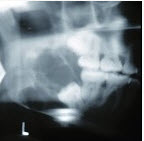

- 单项选择题某患者一侧下颌磨牙区、下颌角及升支部渐进性膨大,按之有乒乓球感。X线片(如图)示多房性密度减低影,分房大小相差悬珠,分隔清晰锐利、阴影边缘呈切迹状,阴影内牙根尖有不规则吸收。该病最可能的诊断是()

A、成釉细胞瘤